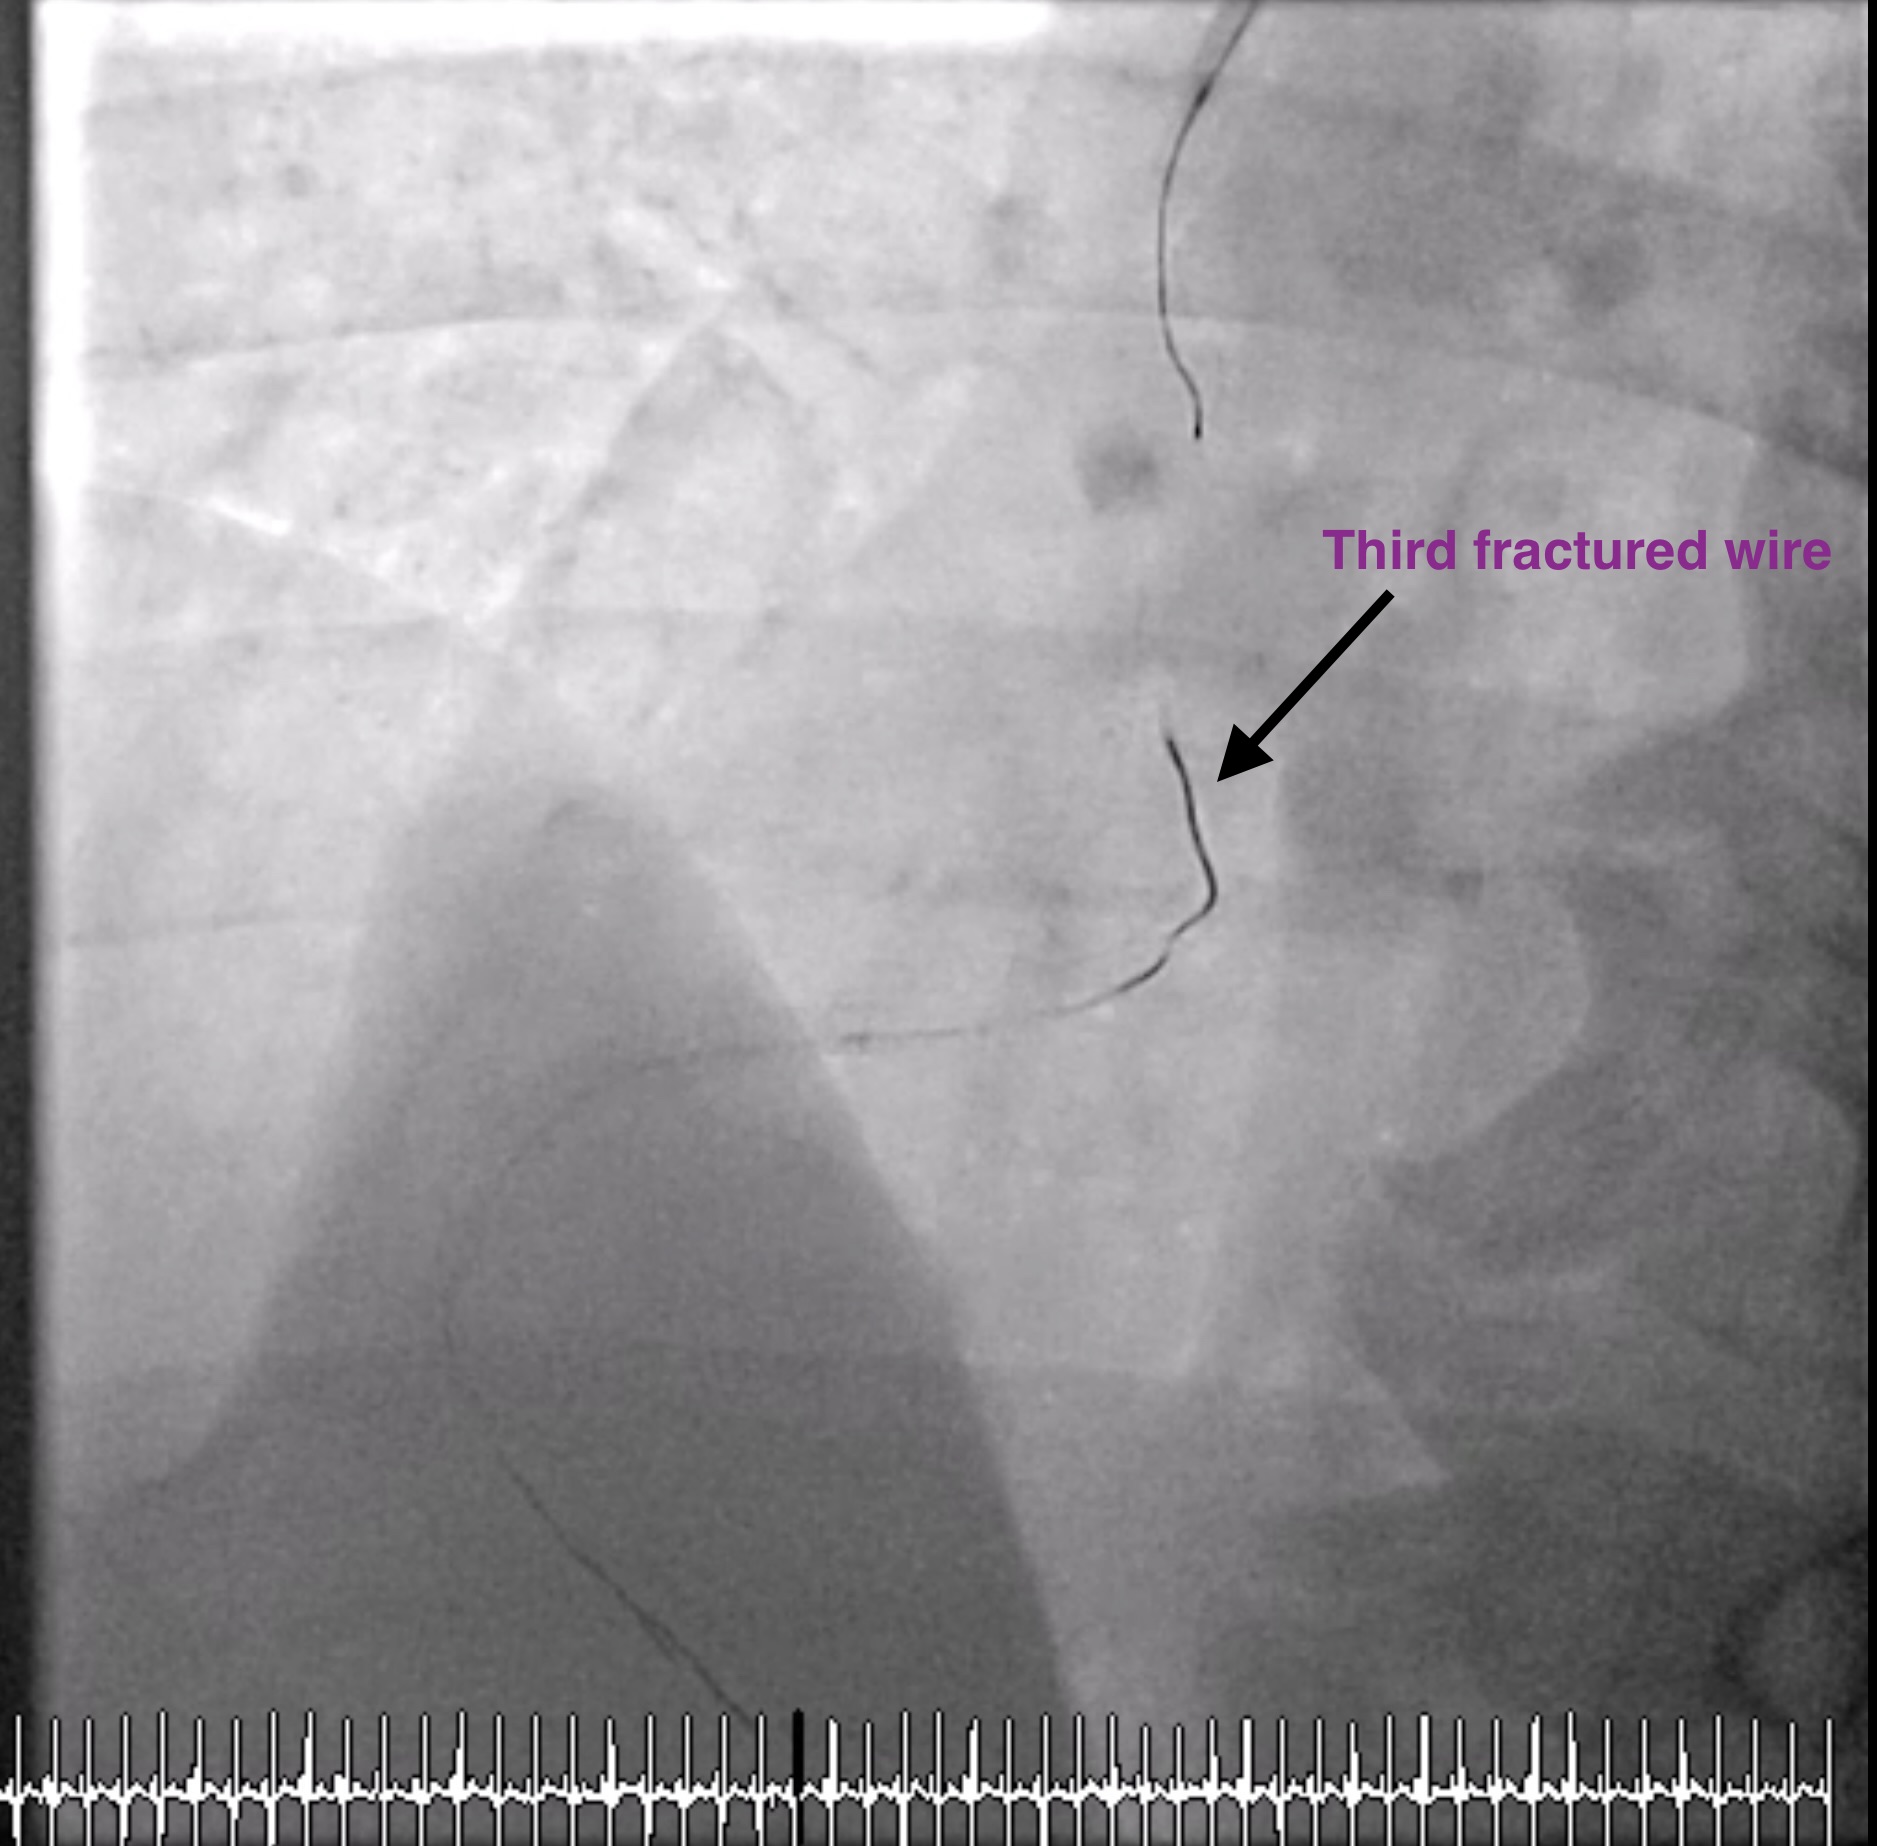

Microcatheter (Finecross) with Fielder XT to RCA, unable to pass the CTO lesion then changed to Gaia 2nd which was unsuccessful too and finally changed to Gaia 3rd. Gaia 3 rd guidewire got stuck at distal RCA. Snare catheter 8 mm was inserted to retrieve Gaia 3rd guidewire which was unsuccessful (Several attempts). Turntrac guidewire and Fielder-XT was inserted across the lesion to twist wire for Gaia 3rd retrieval, but failed and complete fracture of all three wires happened. Snare Size 8 mm was inserted for retrieval but failed.Smaller snare size 7 mm and 4 mm were inserted for retrieval but failed.Left femoral artery puncture with 8 Fr. Sheath. Guiding catheter JR 4.0/7 was used. Snare 8 mm and 15 mm via LFA could retrieve some part of wire. Decided to leave the wire at RCA due to several failed attempts. Angiogram was done before stopping the procedure. As we were removing the catheter, thin stretched guidewires were seen floating in the ascending aorta till descending aorta. Snare 15 mm could remove the wire floating in the aorta after several attempts.Final angiogram showed retained some parts of fractured guidewires and planned to leave it there. The patient was asymptomatic and hemodynamically stable.